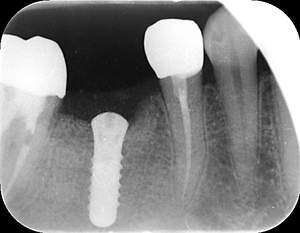

レントゲン写真

- 透過像

| 年齢 | 50代・男性 |

|---|---|

| 主訴 | 右下歯が疼く |

| 治療内容 | ・右下6番インプラント ※1:FGG(遊離歯肉移植術)とは、足りない歯ぐきを上顎から上皮を切り取り移植する外科手術 |

| 治療費 | 合計:902,000円(税込) ■内訳 |

| 治療期間 | 9ヵ月 |

| 治療方針 | 右下の当該歯は歯根破折により保存不可能と診断しました。歯周疾患も伴っていたため抜歯後に骨吸収※1が大きく起こることが予測できました。チタンメッシュ併用骨再生誘導法(GBR※2)を選択しインプラント埋入と同時に行い自然な歯槽骨のラインを再現しました。またGBRを行う際にインプラント辺縁の付着歯肉の減少が起こる為、遊離歯肉移植術(FGG※3)を行い清掃性を考慮した形態に仕上げました。 ■治療方針の解説 治療した右下の歯をレントゲンで撮影したところ根本の部分に黒く写る箇所があり「根尖性慢性周囲炎※1」と診断。また歯周病も進行していました。 ※1 骨吸収・・・歯槽骨という歯を支える骨がなくなっていくこと |

| 担当者所見 | 主訴の右下だけでなく歯茎の腫れ、発赤があり不良補綴や不良充填など他にも治療箇所が多数ありました。プラークコントロールが不良であった為まずはブラッシング指導を行いセルフケアの重要性を理解していただくところからスタートしました。 右下6番の歯はインプラント治療を行なった結果審美的にも機能的にも患者様の満足を得ることができました。骨造成と歯肉移植も行なった為インプラントを支える十分な歯周組織の獲得ができたと思っております。 |